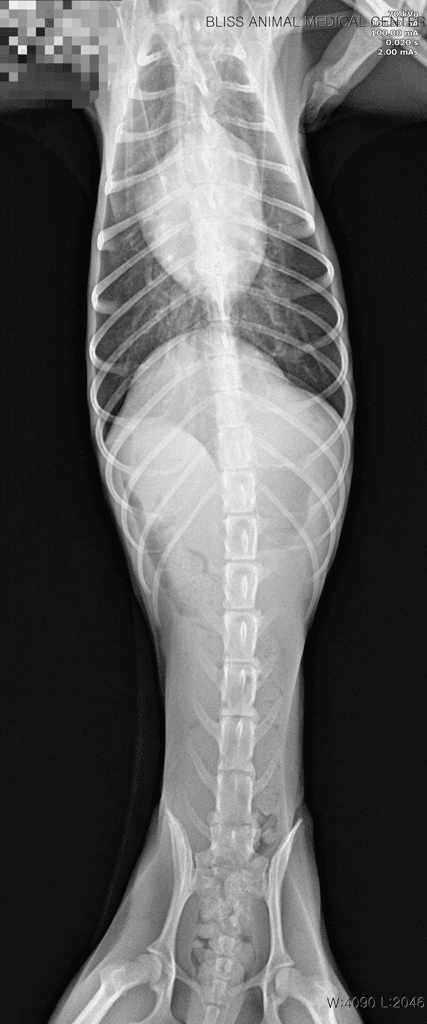

7월 16일에 강아지가 무기력하더니, 17일 새벽에 1번, 병원에서 2번, 내원 후 집에서 1번 총 4번 발작했습니다. 검사해 보니 췌장염도 있고, 심장병(단계 설명은 못 들음), 간 문제 등등 그 외에도 문제가 많이 보여서 수의사 님도 정확히 뭐 때문에 발작을 했는지 확답을 내리지 못 하셨습니다.

이 나이에 이렇게 아픈 것도, 체격/먹는 거에 비해 살이 안 오르는 것도 선천적 요인일 가능성이 높다고 하셨습니다.

주치의 선생의 의견과 비슷하게 현재 발작을 유발할정도의 수치들은 아닙니다.

이런 상황이라면 뇌 외성 원인을 잠정적으로 배제할 수 있는 수준이라 뇌외성 이상 즉, 두개골 내의 이상을 평가하기 위한 MRI 검사가 추천됩니다.

뇌내 이상은 혈액검사에서 특별한 변화를 보이지 않거나 위 자료처럼 애매하게 나오는게 일반적이기 때문입니다.